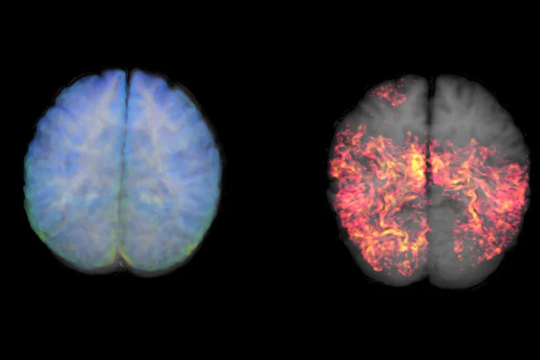

• Xét nghiệm máu để hỗ trợ chẩn đoán Alzheimer‏

Xét nghiệm máu để hỗ trợ chẩn đoán Alzheimer‏